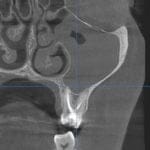

Vilični ili maksilarni sinusi su parne šupljine u telu gornje vilice, koji svojom pozicijom mogu da budu u bliskom kontaktu sa položajem korenova gornjih bočnih zuba. Njihova veličina je individualna i genetski definisana. Mogu da budu manjeg promera i da se ne nalaze u projekciji korenova zuba gornje vilice, a s druge strane mogu da budu izuzetno voluminozni pa da se protežu od korenova prekutnjaka, a ponekad i od očnjaka, sve do poslednjeg kutnjaka u vilici.

Dijagnoza sinuzitisa se postavlja detaljnom anamnezom, kliničkim pregledom, kao i analizom rentgenskih snimaka (snimak paranazalnih šupljina, OPT snimak kao i 3D snimak).